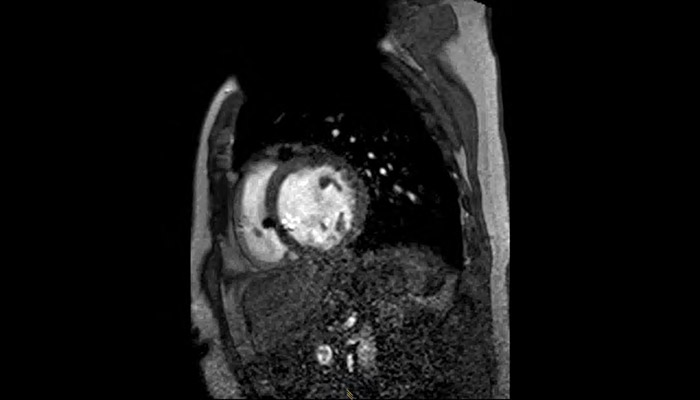

MRI of heart with MR Conditional ICD

A patient with an MR Conditional ICD and suspected myocarditis presented for MRI. This short axis view of the heart is created with an SSFP (steady state free precession) sequence on a Philips Achieva 1.5T system. The cardiac MRI exam reveals normal dimensions and regular function of the right and left ventricle. Note the ICD lead in the right ventricle (arrow) and the signal void in the left pectoral region, indicating the ICD-IPG (asterisk). Courtesy of Dr. Sommer.